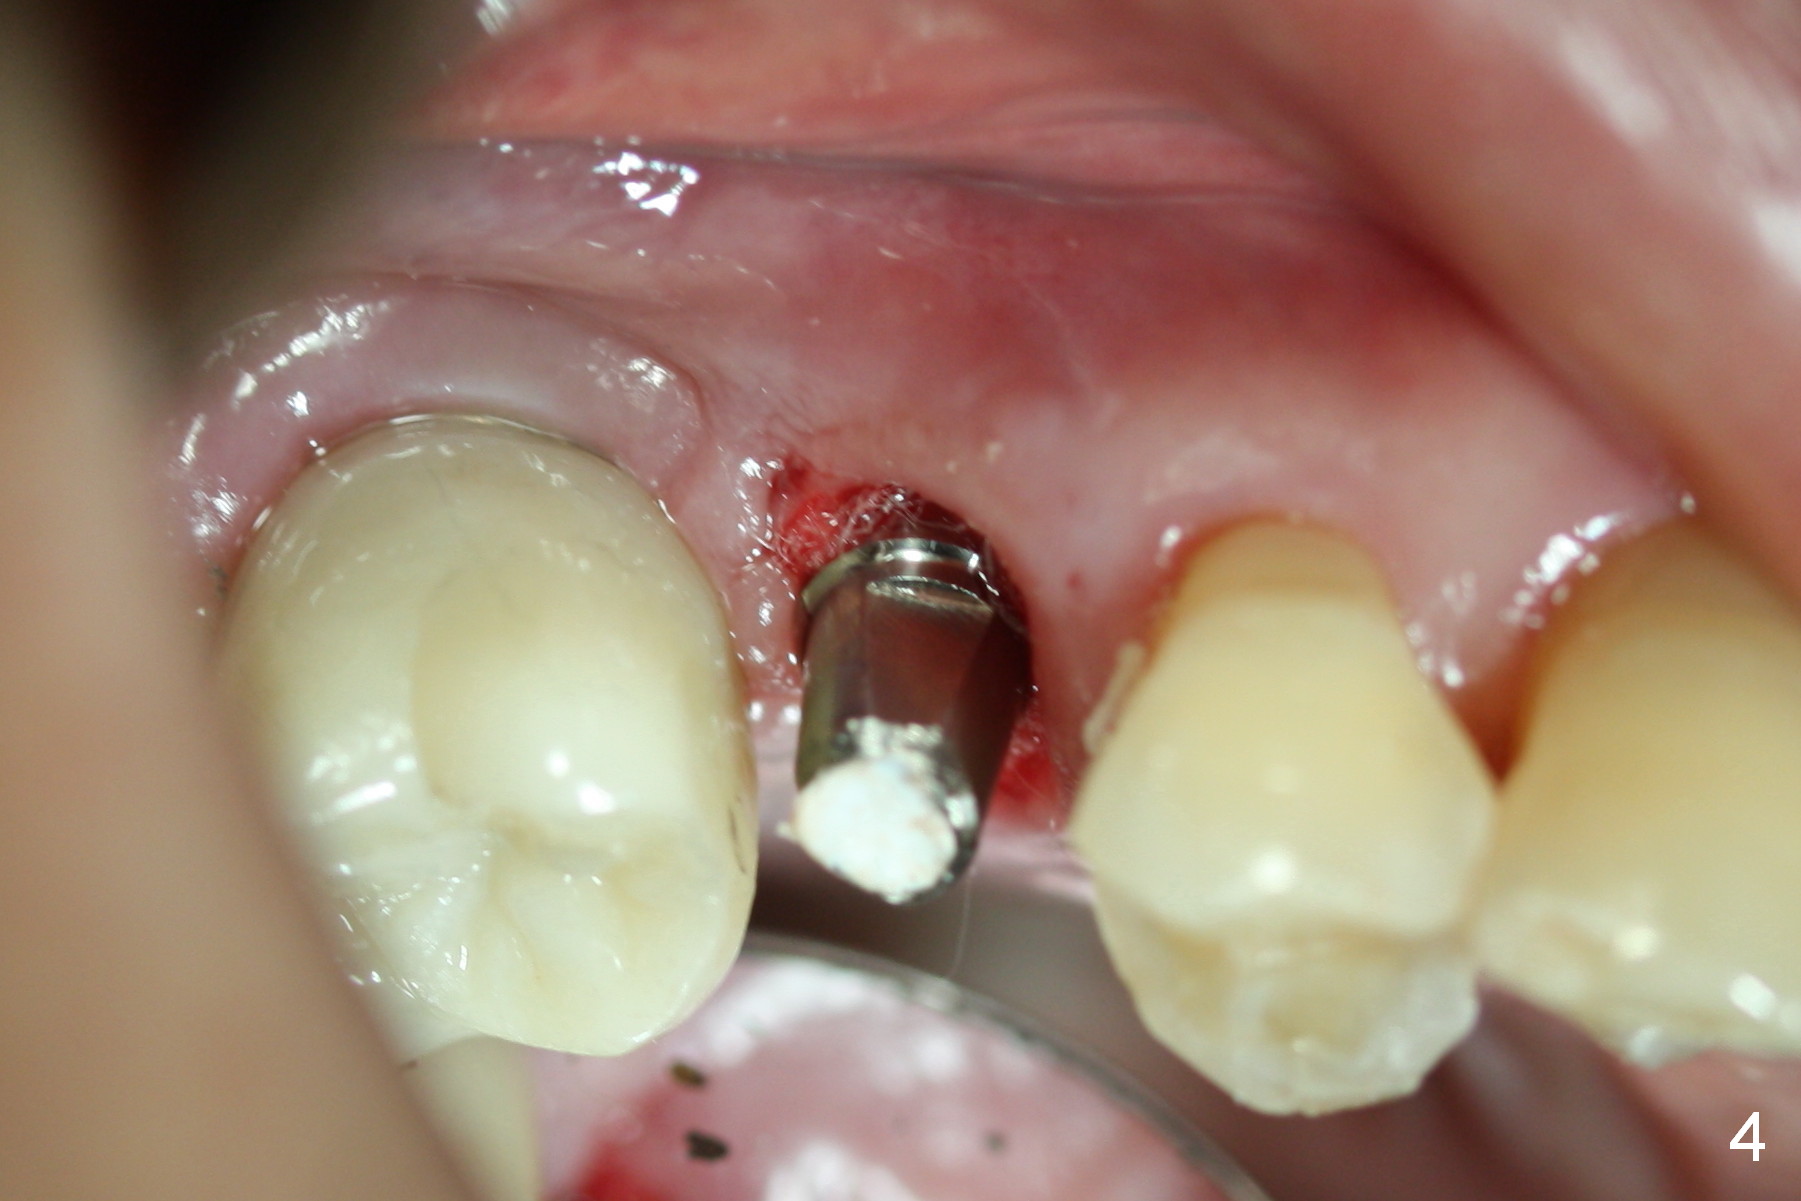

The distal buccal (Fig.1) and palatal (Fig.2) papillae (*) are recessive at the tooth #4. Following extraction and use of 3.8 mm Magic Drill, a 4.5x13 mm implant is placed lower than the mesial crest (Fig.3) to reduce the chance of the distal implant thread exposure. The latter is a measure to decrease peri-implantitis. A 4.5x5.7(4) mm pair abutment is placed (Fig.4,5). The remaining socket is filled with allograft/Osteogen placement. The large space between #3 and 4 implants is occupied by the healthy gingiva, where bone graft cannot get in.